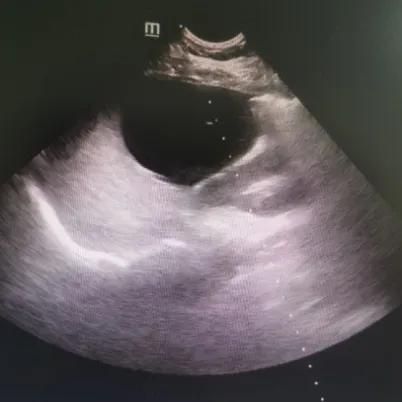

经过充分的术前评估,完善的术前相关检查,手术在实时超声引导监测下进行,动态观察穿刺针的位置,精确穿刺、精确抽吸,共抽出液体162ml,然后注入3ml利多卡因,停留3分钟后抽出,而后注入13ml无水乙醇,停留5分钟后抽出13ml液体,超声监测囊肿消失。整个手术过程病人处于完全清醒状态下,手术过程近1小时,术后留观1小时,患者无明显出血及不良反应后,在家属陪同下出院。(附肝囊肿硬化治疗前后超声图对比,图1、图2)

图1:硬化治疗前